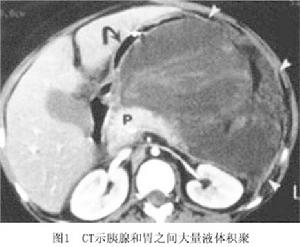

2.ERCP對於胰外瘺要了解瘺管與胰管及周圍臟器的關係,瘺管有無分叉,胰瘺引流是否通暢並對端瘺和側瘺進行區分可行瘺管造影進行觀察。對於瘺管造影不滿意和胰腺假性囊腫的病人需行ERCP檢查(圖2)。

在進行ERCP檢查的同時對於近端胰管有狹窄的還可行內支架治療,這一方法多可促進胰外瘺的自愈在進行ERCP或瘺管造影時,應注意避免誘發胰腺炎。有報導在檢查前後使用生長抑素及其類似物預防和治療並發胰腺炎。